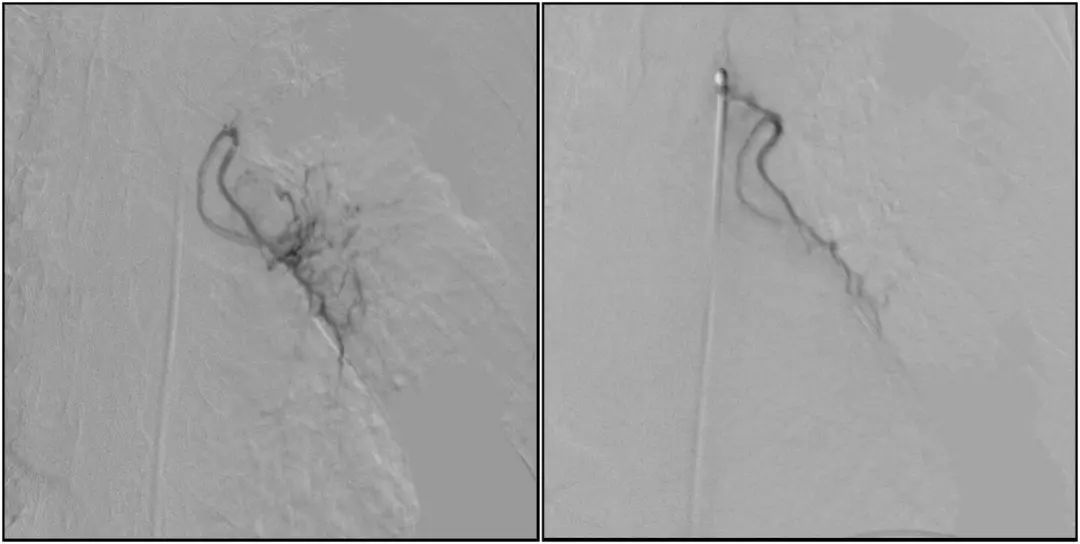

在微導絲的配合下,先后分別超選擇①至3支左側支氣管動脈腫瘤供血動脈,經微導管推注栓塞微粒球栓塞腫瘤動脈。栓塞結束后,再次用移動式平板介入中C做造影檢查,見腫瘤染色消失。

術前術后對比影像